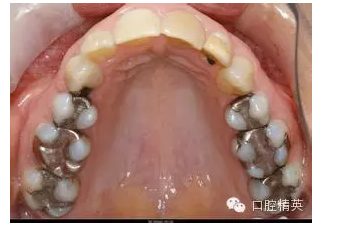

最常見的牙齒問題之一——齲齒,也就是蟲牙。牙齒黑了,有洞了,到了牙科要補(bǔ)上。這時(shí)就面臨了一個(gè)選擇問題:補(bǔ)一個(gè)什么樣的呢?好多患者很是信任醫(yī)生:大夫你說哪個(gè)好就來哪個(gè)吧!或者,大夫你幫我選一個(gè)吧!應(yīng)該聽專業(yè)人士的,但是花了錢,還是應(yīng)該弄清楚花在了哪里,這樣心里才舒坦。

現(xiàn)在主要有兩種材料:銀汞合金和樹脂。銀汞合金補(bǔ)一顆牙100-300塊錢,樹脂則要100-800不等,相差還是蠻懸殊的。

銀汞合金可以說是歷史最為悠久的補(bǔ)牙材料之一,極其經(jīng)典,應(yīng)用了一百多年。主要優(yōu)點(diǎn)是硬度高、價(jià)格低廉。缺點(diǎn)是需要磨牙的量相對(duì)大,這一點(diǎn)對(duì)于很多患者來說無法忍受;另外和牙齒之間沒有粘接性,很難和牙齒緊密相接,容易脫落或繼發(fā)新的齲齒;不美觀,即使進(jìn)行了拋光處理,也只是金屬色,有的使用時(shí)間長了呈黑色,放在嘴里那是相當(dāng)?shù)拿黠@;最后一個(gè)缺點(diǎn)就是銀汞合金相對(duì)于牙齒來說太硬了一點(diǎn),以致于如果下牙補(bǔ)了一塊銀汞,與它相對(duì)的上牙會(huì)發(fā)生比較厲害的磨損,而合金巋然不動(dòng)。

QQ圖片20150716163653.png

所以目前來看樹脂除了價(jià)格以外基本已經(jīng)全面優(yōu)于銀汞合金了,目前補(bǔ)牙領(lǐng)域的三大趨勢(shì)之一就是徹底淘汰銀汞合金。但費(fèi)用有時(shí)也確實(shí)是唯一和最大的問題,銀汞便宜醫(yī)保還能報(bào)銷,樹脂貴還都是自費(fèi)的。畢竟一分錢一分貨,只能希望國產(chǎn)的牙科材料在性能上能更進(jìn)一步,把市場(chǎng)從進(jìn)口貨上奪回來,為百姓造福。